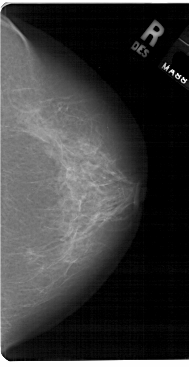

A_1726_1.LEFT_MLO

LEFT_MLO LINES 5491 PIXELS_PER_LINE 2911 BITS_PER_PIXEL 12 RESOLUTION 43.5 OVERLAY